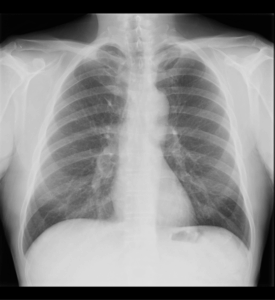

Rx PA de tórax